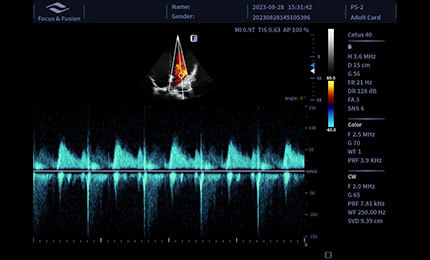

Technologia obrazowania ultrasonograficznego z inwersją impulsów i kontrastowaniem pozwala dokładnie wyodrębnić drugi harmoniczny kontrastowych mikropęcherzyków, co umożliwia uzyskanie obrazowania z wysokim stosunkiem kontrastu do tkanki oraz zapewnia bardziej szczegółową diagnozę kliniczną.